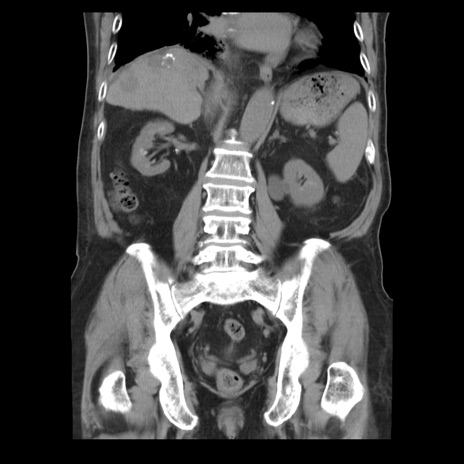

症例21(冠状断像)

【症例】70歳代男性

【主訴】腹痛

【現病歴】肝硬変・肝細胞癌にてかかりつけの方。約9時間前に食後より腹痛出現。症状が徐々に増悪し、嘔吐出現したため来院。

【既往歴】肝硬変、肝細胞癌(RFA、TACE後)

【身体所見】意識清明、表情苦悶様、BT 36℃、BP 129/78mmHg、P 88bpm、SpO2 97%(RA)、右上腹部から心窩部にかけて圧痛あり、反跳痛なし、筋性防御あり。

【データ】WBC 5800、CRP 0.16